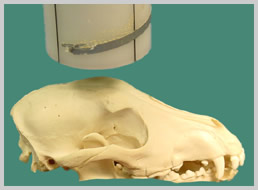

This technique is similar to the ventro-dorsal technique, but with

the patient in sternal recumbency. An intra-oral technique can also

be performed with less superimposition.

Positioning for DV skull extra-oral

technique